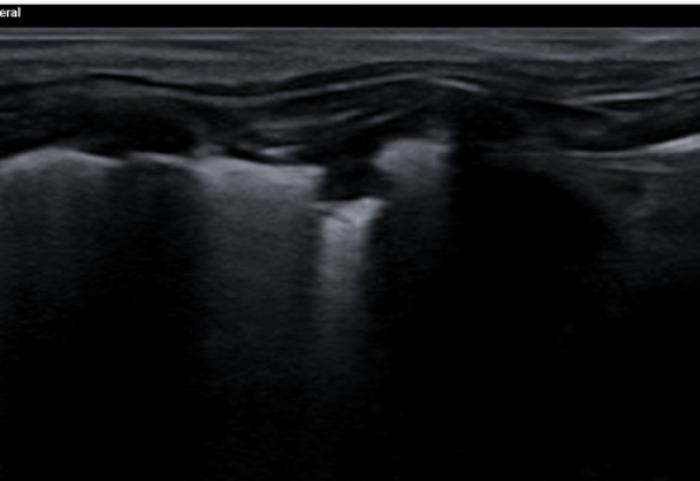

Signo nodular

Consiste en una consolidación de aspecto circular a menudo de anecoicos a hipoecoicos con rara aparición de broncogramas en su interior. Distalmente al signo nodular observamos una línea cóncava hiperecogénica llamada línea C y un refuerzo posterior o signo de brillo en la profundidad del campo. Este hallazgo es común en neoplasias primarias o metastásicas, granulomas fúngicos o abscesos. Es un signo de especial importancia cuando tenemos un paciente con historial oncológico previo o en el protocolo de búsqueda de metástasis. Los nódulos observados veremos cómo se desplazan de izquierda a derecha de la imagen con la respiración del paciente, haciendo patente que se encuentran a nivel pulmonar y no de la pared costal, en cuyo caso no se desplazaran mientras el transductor se encuentre inmóvil (Figura 16A-D).